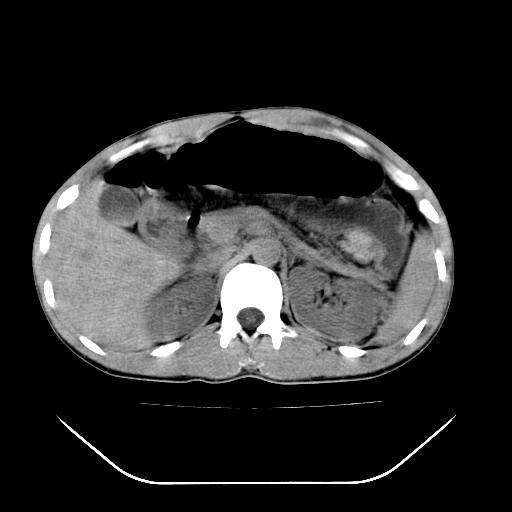

m-25y 高空堕落 12 月5号

12月7号病人尿量200ml/24h 急查双肾ct

左肾挫裂伤并肾周血肿;

12月7号

肝肾间隙可见液区,建议手术探查;

左肾挫裂伤并肾周血肿

支持 : 左肾挫裂伤并肾周血肿

支持:1、左肾挫裂伤并肾周血肿;

2、少量腹水;

3、左肾旋转不良;

4、反射性肠淤张。

除了1:左肾挫裂伤并肾周血肿;

2:少量腹水

第二次ct检查后:临床医生腹水穿刺后考虑肠系膜动脉破裂,后实行剖腹探查:于空肠距离十二指肠90cm处发现肠管破裂,破裂口较小;修补后关腹。